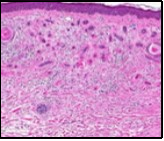

Lesions are generally superficial and infrequently invade lower dermis. Tendency for peri-neural or intra-neural infiltration, cogitated in adjunctive cutaneous carcinomas, is exceptional in desmoplastic trichoepithelioma. Nevertheless, desmoplastic trichoepithelioma can be exemplified as a component of particularly desmoplastic, cutaneous carcinomas demonstrating foci of peri-neural involvement 4, 5. Figure 1, Figure 2, Figure 3, Figure 4, Figure 5, Figure 6, Figure 7, Figure 8.

Figure 2.Desmoplastic trichoepithelioma delineating cords and nests of basaloid cells, few horn cysts and a circumscribing fibrotic stroma 9.